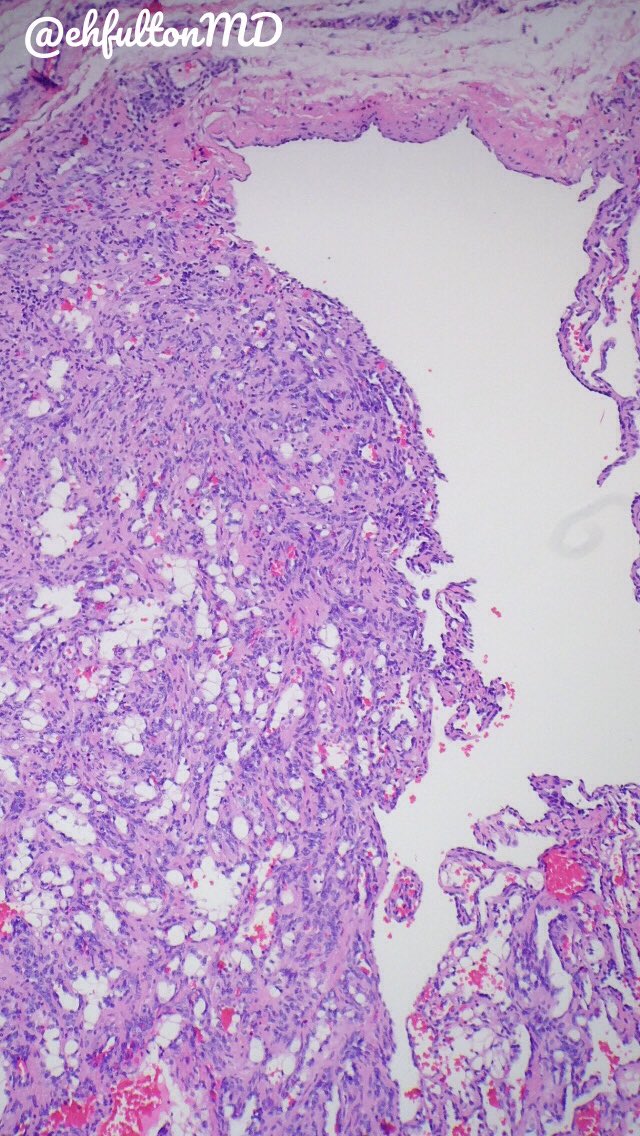

50 yo male, elevated AST/ALT. Beautiful classic histology for...? What’s your ddx? #liverpath